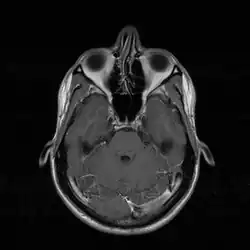

In de neusholte zelf bevinden zich aan weerszijden symmetrisch drie dunne, met slijmvlies beklede botplaten (conchae of neusschelpen), die het inwendige oppervlak van de neusholte sterk vergroten. Deze plooien vangen de kleinere deeltjes die in de ingeademde lucht aanwezig zijn op. Ze zijn goed doorbloed en verwarmen zo de ingeademde lucht, zodat deze op lichaamstemperatuur komt. Ook zorgen ze voor een zekere turbulentie in de luchtstroom zodat geurstoffen worden getransporteerd naar het reukslijmvlies. Dit slijmvlies bevindt zich boven in de neusholte, onder de schedelbasis en tussen de oogkassen.

De linker- en rechterneusholte zijn van elkaar gescheiden door het neustussenschot of neusseptum, dat bestaat uit een voorste deel van kraakbeen en een achterste gedeelte van bot. In het slijmvlies van het tussenschot lopen veel oppervlakkige bloedvaatjes en de meeste neusbloedingen vinden hier hun oorsprong. De vaatkluwen in het slijmvlies van het onderste deel van het neusseptum, locus Kiesselbachi, vormt een predilectieplaats voor neusbloedingen.

In de neusholte draineren twee andere organen, de bijholten en de traanklieren.

Aan de laterale zijden draineert de kaakholte (sinus maxillaris). Boven in de neusholte draineren de voorhoofdsholte (sinus frontalis) en de zeefbeenholtes (sinus ethmoidici).